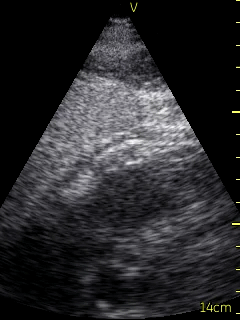

A transthoracic echo (TTE) was ordered for the morning following admission, and a bedside echocardiogram was conducted with a hand-held ultrasound unit (VScan, GE), revealing a dilated hypokinetic right ventricle and grossly normal left ventricular systolic function. The point-of-care cardiac ultrasound (POCUS) led to a new Differential: PE and ACS/right ventricular infarct.